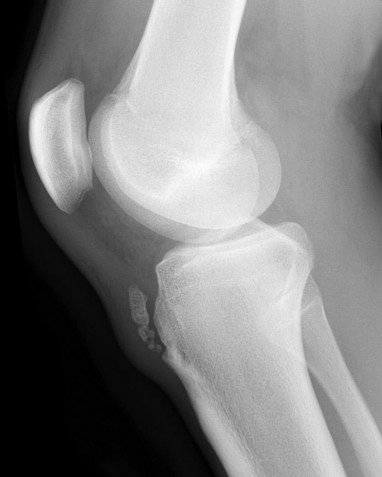

Case courtesy of Assoc Prof Frank Gaillard, Radiopaedia.org From the case rID: 7511

Osgood-Schlatter Disease

This condition is an example of a juvenile apophysitis - inflammation of the area around the growth plate. It is a common overuse condition in children which presents as inflammation of the tibial tubercle apophysis with repetitive extension.15 The exact mechanism of this is unclear, though likely due to repetitive strain across the apophysis due to imbalance of the pull of the quadriceps muscle. The resulting inflammation presents with tenderness as well as pain, with forceful extension directly over the tibial tubercle. While traditionally taught as a condition of males, recent literature reveals no sex difference.16 History and clinical exam is sufficient for diagnosis, but x-rays can be obtained if it is part of a larger differential or if there is concern for a full avulsion. X-rays may demonstrate avulsion so should be obtained if this is considered.9 NSAIDs, rest, and ice are typically effective. Quadriceps and hamstring stretches should be incorporated into routine for all young athletes who have an open physis. Use of a patellar strap can also help decrease pain in some patients. The condition is generally self-limited with resolution after closure of the physis. Conservative management is successful in >90% of patients but operative management is indicated in some patients.16 Prominent tubercle can become permanent and can be a cosmetic concern. Arthroscopy can be performed to intervene on particularly resistant cases.15